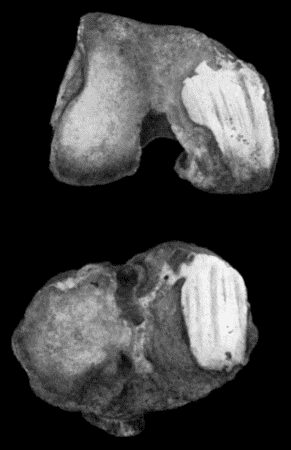

| 124. | Tuberculous Osteomyelitis of Os Magnum | 456 |

| 125. | Tuberculous Disease of Tibia | 457 |